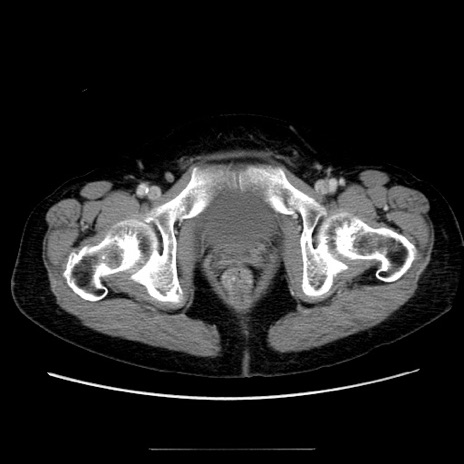

冠状断像

【症例】70歳代女性

【主訴】お腹が張る

【現病歴】1週間くらい前から腹部膨満の自覚あり。昨日夜から増悪したため、本日救急外来受診。

【身体所見】意識清明、BT 36.5℃、BP 165/106mmHg、HR 80bpm、SpO2 98%、腹部:膨満、軟、自発痛・圧痛なし、触診にて不快感あり、腸蠕動音:減弱

【データ】WBC 12600、CRP 1.04